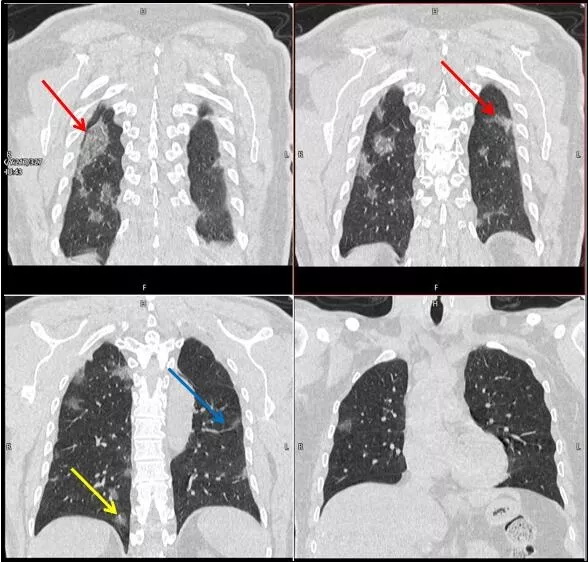

武漢大學(xué)中南醫(yī)院影像科副主任張笑春教授發(fā)現(xiàn),目前武漢市家庭聚集性發(fā)病較多,而且大多起病隱匿,一次甚至多次核酸陰性,無(wú)任何臨床癥狀,CT檢查卻已顯示為病毒性肺炎特征。

CT為當(dāng)前首選篩查與診斷的主要影像學(xué)手段,胸部CT的病毒性肺炎檢出率高。